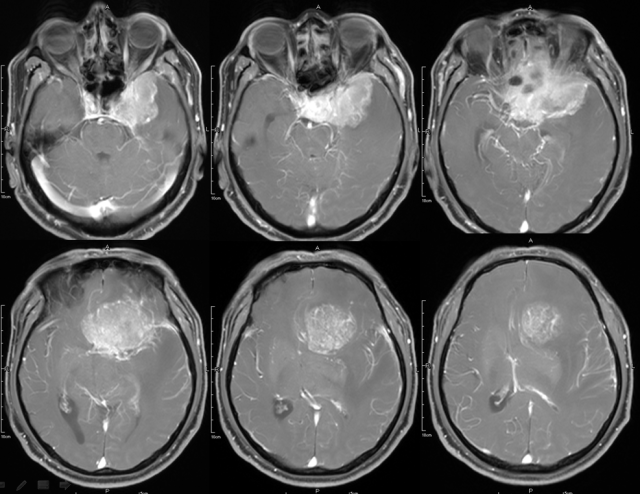

脑膜瘤

图片尺寸640x494